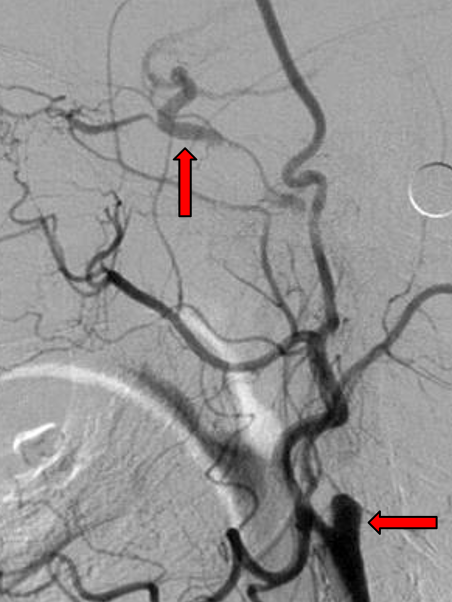

腔内开通技术要点

① 器械选择

导引导管/长鞘建立通路

冠脉CTO导丝(如Progress 200T)突破纤维帽

② 脑保护

近端球囊阻断(如TCAR系统)减少栓塞

典型病例与教训

病例1(男性,76岁)

Wingspan支架植入后血流改善,但近端夹层需追加Precise支架